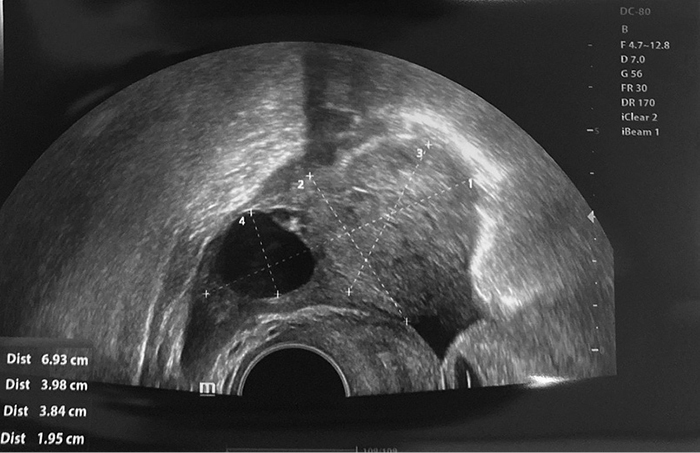

A 25-year-old nulliparous woman with regular menstrual periods consulted a gynecologist because of pain in the left lower abdomen, especially when inserting a menstrual cup or tampon. This pain had persisted for a year. She had no vaginal discharge, fever, dysuria, frequent urination, or diarrhea. Additionally, this woman was consulted by an endocrinologist and a dermatologist for hair loss. Testosterone level was elevated, and she was taking spironolactone for six months. CA125 level and other laboratory values were normal. Transvaginal ultrasound showed larger bilateral ovaries, left ovary enlarged to 4.5x2.5 cm with multiple cysts 2–3 cm in size with echo positive inserts, and right ovary also enlarged to 6.9x4.0 cm with cyst 4.0x3.8 cm in size filled with opaque content (Figure 1, 2).

Figure 2. Left ovary

A pelvic MRI showed three dermoid cysts on the right ovary, the largest of which was 3.2 cm. The left ovary also showed five dermoid cysts, the largest 4.2 cm diameter. A bilateral laparoscopic ovarian cystectomy was performed. During the operation, dermoid cysts containing hair and fat were found in both ovaries. With the help of bipolar coagulator and forceps, three right ovarian dermoid cysts and five left ovarian dermoid cysts were enucleated. To preserve the largest possible ovarian reserve, the ovaries were minimally coagulated and sutured to ensure hemostasis. Histopathological findings confirmed mature benign teratomas on both sides with no immature tissue. These non-malignant tumors had multi-layered squamous epithelium, mature adipose, and nervous tissue with inclusions of keratin masses. After 6 and 12 months, the patient came for a follow-up checkup. At both time points, ultrasound showed that the bilateral ovaries were normal in size with sufficient reserve (the antral follicle count was 6 to 8 in both ovaries). Still, a minor about 10 mm hyperechogenic mass in the right ovary (without positive growth dynamic) was a probable sign of recurrent dermoid cyst.